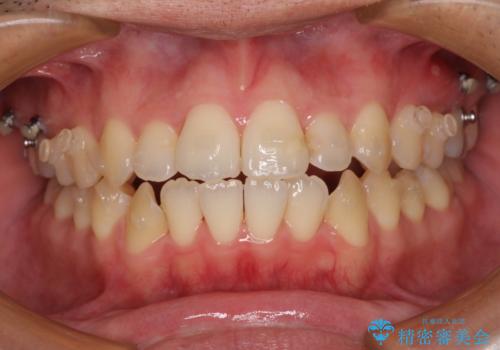

- インビザライン

- 1年9ヶ月

開咬の治療は、前歯を閉じるように動かすとともに、上下臼歯を圧下(骨内にめり込ませる)させることで進めて行きます。

インビザラインは臼歯の圧下を効果的に行えるため、インビザラインを用いて矯正治療を行うこととしました。また、アンカースクリューを用いて、口元の突出感の改善を図りました。